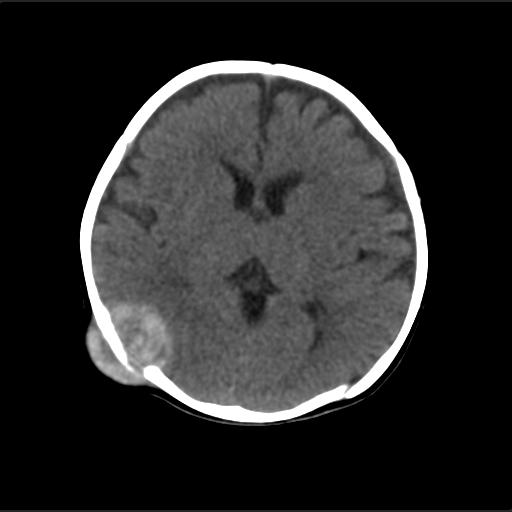

f2m出生已来可见右侧枕部见包块,质地软,无外伤史。包块处ct值16-67hu,大小约3.1x3.2cm左右。

局部颅骨破坏,并以破坏为中心的高密度肿块影,内示软骨影,考虑颅骨软骨瘤.

产伤?---骨膜下血肿机化?骨折?---外部性脑积水

仔细看颅骨是分离

骨质还算完整。

猜一个

考虑血肿的机化。

病灶位于颅缝区,向内外生长,边缘光整。考虑脑膜瘤

血肿机化可能性 比较大,伴双侧额颞顶部硬膜下积液。估计产伤引起